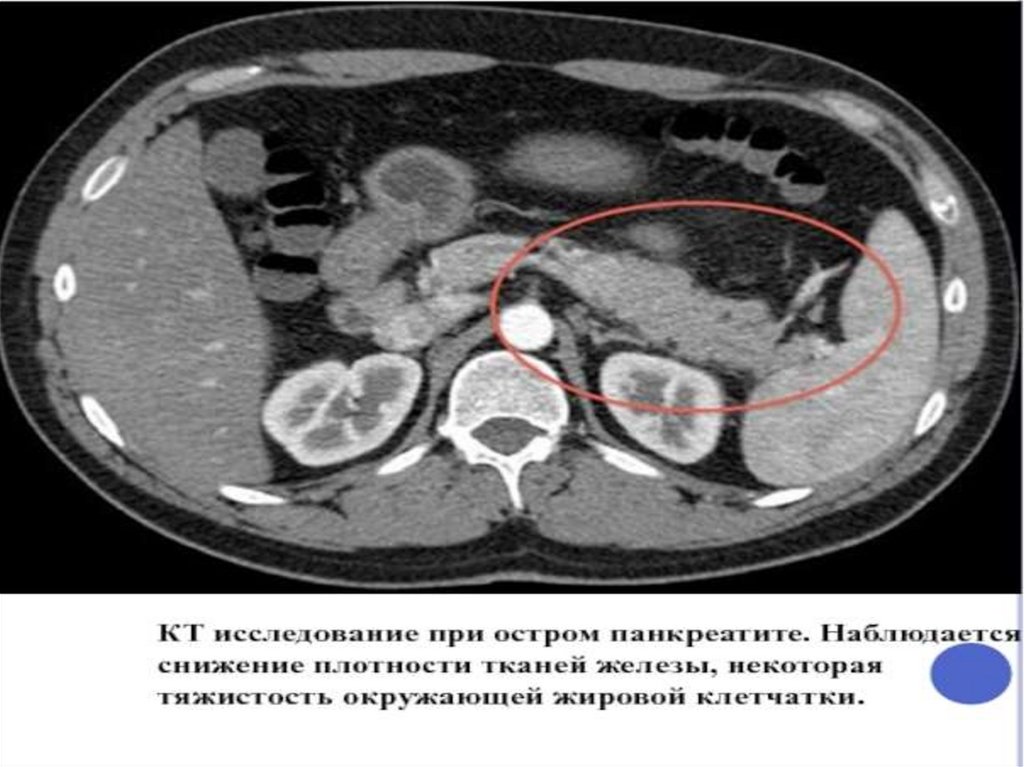

ОСТРЫЙ ПАНКРЕАТИТ